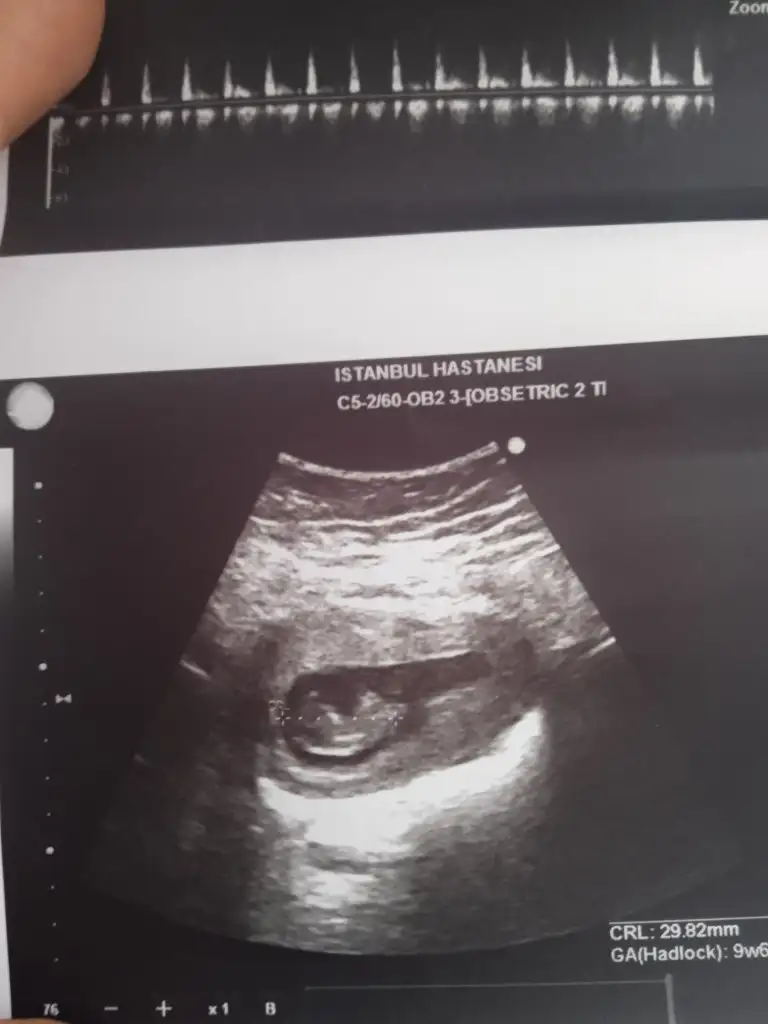

Başka foto yok mu? Bunlar hiç net değil. Bebeği görmem lazım.Canım banada bakarmisin kime yazsam cevap yok ya bu hafta öğrenmek istiyorum artık bir kızım var gönlümden geçen erkek tabiki Allah hayırlısını ve sağlıklisini nasip etsin herkese

Yok canım en son bunları verdi doktor iki ayrı doktor bu fotoğraf ta belli olmuyormu dokuz haftalık en son gittiğim on bir olmuştu ama doktorun ultrason cihazı böyle resim verdiBaşka foto yok mu? Bunlar hiç net değil. Bebeği görmem lazım.

Kafası ne tsrafta anlasam söylerim de anlayamadımYok canım en son bunları verdi doktor iki ayrı doktor bu fotoğraf ta belli olmuyormu dokuz haftalık en son gittiğim on bir olmuştu ama doktorun ultrason cihazı böyle resim verdi

Diğer sefer gittiğimde kafası bilgisiyarda sağ taraftaydi şu gönderdigim fotoğraf varya belli olan o pozisyon onun diğer tarafa dönmüştüKafası ne tsrafta anlasam söylerim de anlayamadım

İşte net görsem söylerim bakın bu arkadaşta bebek net görünüyor mesela.Diğer sefer gittiğimde kafası bilgisiyarda sağ taraftaydi şu gönderdigim fotoğraf varya belli olan o pozisyon onun diğer tarafa dönmüştü

Sizin bence erkek ama ben doktor değilim sadece kendi tecrübelerime dayanarak söylüyorum.Canım bana da bakar mısın 11+1